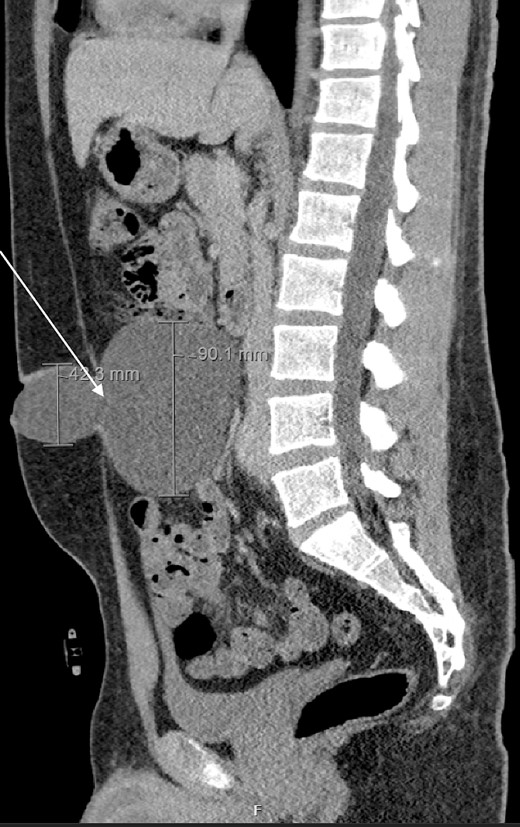

We present the case of a 26-year-old man who presented to the general surgery outpatient clinic with intermittent peri-umbilical pain, and the presence of a soft swelling palpable at his umbilicus. There was a positive cough impulse consistent with a true umbilical hernia and the patient described no previous medical or surgical history. An abdominal ultrasound scan visualized a large thin-walled serous fluid collection tracking into the peritoneal cavity (95 mm × 87 mm × 97 mm) (Fig. 1). Computed tomography (CT) of the abdomen and pelvis with contrast reported a large bi-lobed cystic mass centred at the right side of the mesentery, with herniation of part of the cyst along the umbilicus. Displacement of the small bowel with anterior extension into the abdominal wall was seen with the suggestion of posterior extension into the right retroperitoneal space (Figs 2 and 3). The patient underwent routine pre-operative work up and the cyst was excised through a midline para-umbilical laparotomy (Fig. 4) given the concern of retroperitoneal involvement. Intra-operatively, the hernia neck and the root of the cyst were found at the base of the umbilical cicatrix with no attachment to the mesentery. The cyst was loculated and filled with clear fluid. It was dissected off the peritoneal tissues and off from the posterior umbilical skin prior to removal. There was evidence of rupture of one of the locules and clear fluid was drained.